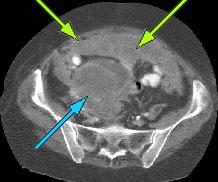

HELICAL CT FINDINGS: The CT was performed on AIC’s multi-slice helical CT (MSCT) scanner. Images with 5 mm collimation were obtained before, immediately following and 5-10 minutes after power injection of IV contrast. Fig. 1 demonstrates large bilateral pleural effusions (red arrows) with secondary compressive atelectasis of the lower lobes (yellow arrow). Fig. 2 shows large amount of ascites (arrows). Fig. 3 shows a large heterogeneous complex pelvic mass (blue arrow) and a large amount of peritoneal masses consistent with omental metastasis known as “omental caking” (green arrows).